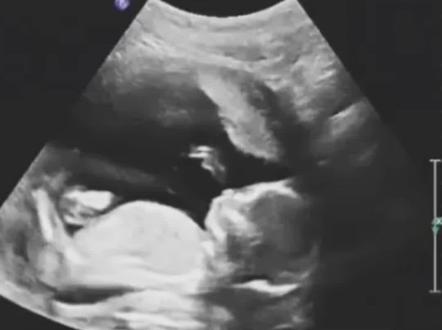

你有没有想过这样一个问题,孕妇怀孕破水为啥叫羊水?破了为啥不叫人水或者其他水?羊水为什么叫羊水?羊水是宝宝的生命之水,之所以被称为羊水,有这么几种说法,第一,羊水这个词是一个古名词,在古字中,羊和羊是相通的, 羊代表太阳,也就是代表人类的生命。开始最开始称羊水,后来经转化演变,慢慢变成了羊水。第二,传说羊水起源于羌族, 以前的人们对羊特别喜爱,因此将羊水比喻成婴儿水。第三,根据西医的说法,是羊膜内的液体。古希腊人认为宝宝出生时包裹在身上的膜和羊肠相似度很高,因此把羊膜里面的液体称为羊水。不管是哪种说法,如今我们都习以为 长的称之为羊水了。羊水是供养宝宝生命不可或缺的重要部分,其中主要成分是水,水含量达到百分之九十八, 同时也存在有少量的无菌眼泪、有积物荷尔蒙以及脱落的胎儿的细胞。羊水到底有什么作用?首先,孕妇的身体在活动时难免大幅度摇晃,肚子里的羊水就能对胎儿起到缓冲和保护作用,减少外部给宝宝带来的伤害。 第二,羊水能起到一个润滑剂的作用,防止宝宝在子宫内发生肢体粘连,促进健康发育。第三, 宝宝通过吞咽羊水,排出羊水来锻炼自己的呼吸和消化能力,从而促进肺部和消化功能的发育,并且实现羊水的循环。羊水是恒温的,可以稳定子宫内的温度,让宝宝处在一个相对适宜的温度里面,避免 受到外界温度的影响。第五,羊水能缓解胎儿在子宫内的活动给妈妈带来的不适感。第六,妈妈生产时,羊水能起到一定的润滑的作用,也减轻了新生胎儿与皮肤的摩擦。 第七,羊水形成的水能还能缓和子宫颈的扩张。第八,羊水中的抑菌物质能降低生产时妈妈和宝宝感染的几率。现在还有一些临床开始研究从羊水中提取干细胞治疗疾病。 羊水中的细胞含量本身不多,更多更丰富的钙细胞都在胎盘和脐带中,生命起源之处都是珍贵的宝贝。

你有没有想过这样一个问题,孕育着胎儿的水为什么要叫羊水,而不是其他的水?其实羊水是宝宝的生命之水。 之所以被称为羊水,有这么几种说法,第一是谐音,说,谐音又分为两种,一种是羊水,意思非常直白,取滋养、 养育婴儿的意思。另外一种是羊水,这个词是一个古名词,在古字中,羊和羊是相通的,羊代表太阳, 也就是代表人类的生命,起初称之为羊水,后来经转化演变,慢慢变成了羊水。第二,传说羊水起源于羌族,以前的人们对羊特别喜爱,因此将羊水比喻成婴儿水。第三,根据西医 的说法,是羊魔内的液体。古希腊人认为宝宝出生是包裹在身上的魔,和羊肠相似度很高,因此把羊魔里面的液体称为羊水。不管是哪种说法, 如今我们都习以为常地称之为羊水了。羊水是供养宝宝生命不可或缺的重要部分,其中主要成分是水,水含量达到百分之九十八, 同时也存在着少量的无机盐类有机物、荷尔蒙以及脱落的胎儿细胞。那么你知道羊水到底有什么作用吗?咱们下期再聊这个话题,老铁们可以在评论区留言。